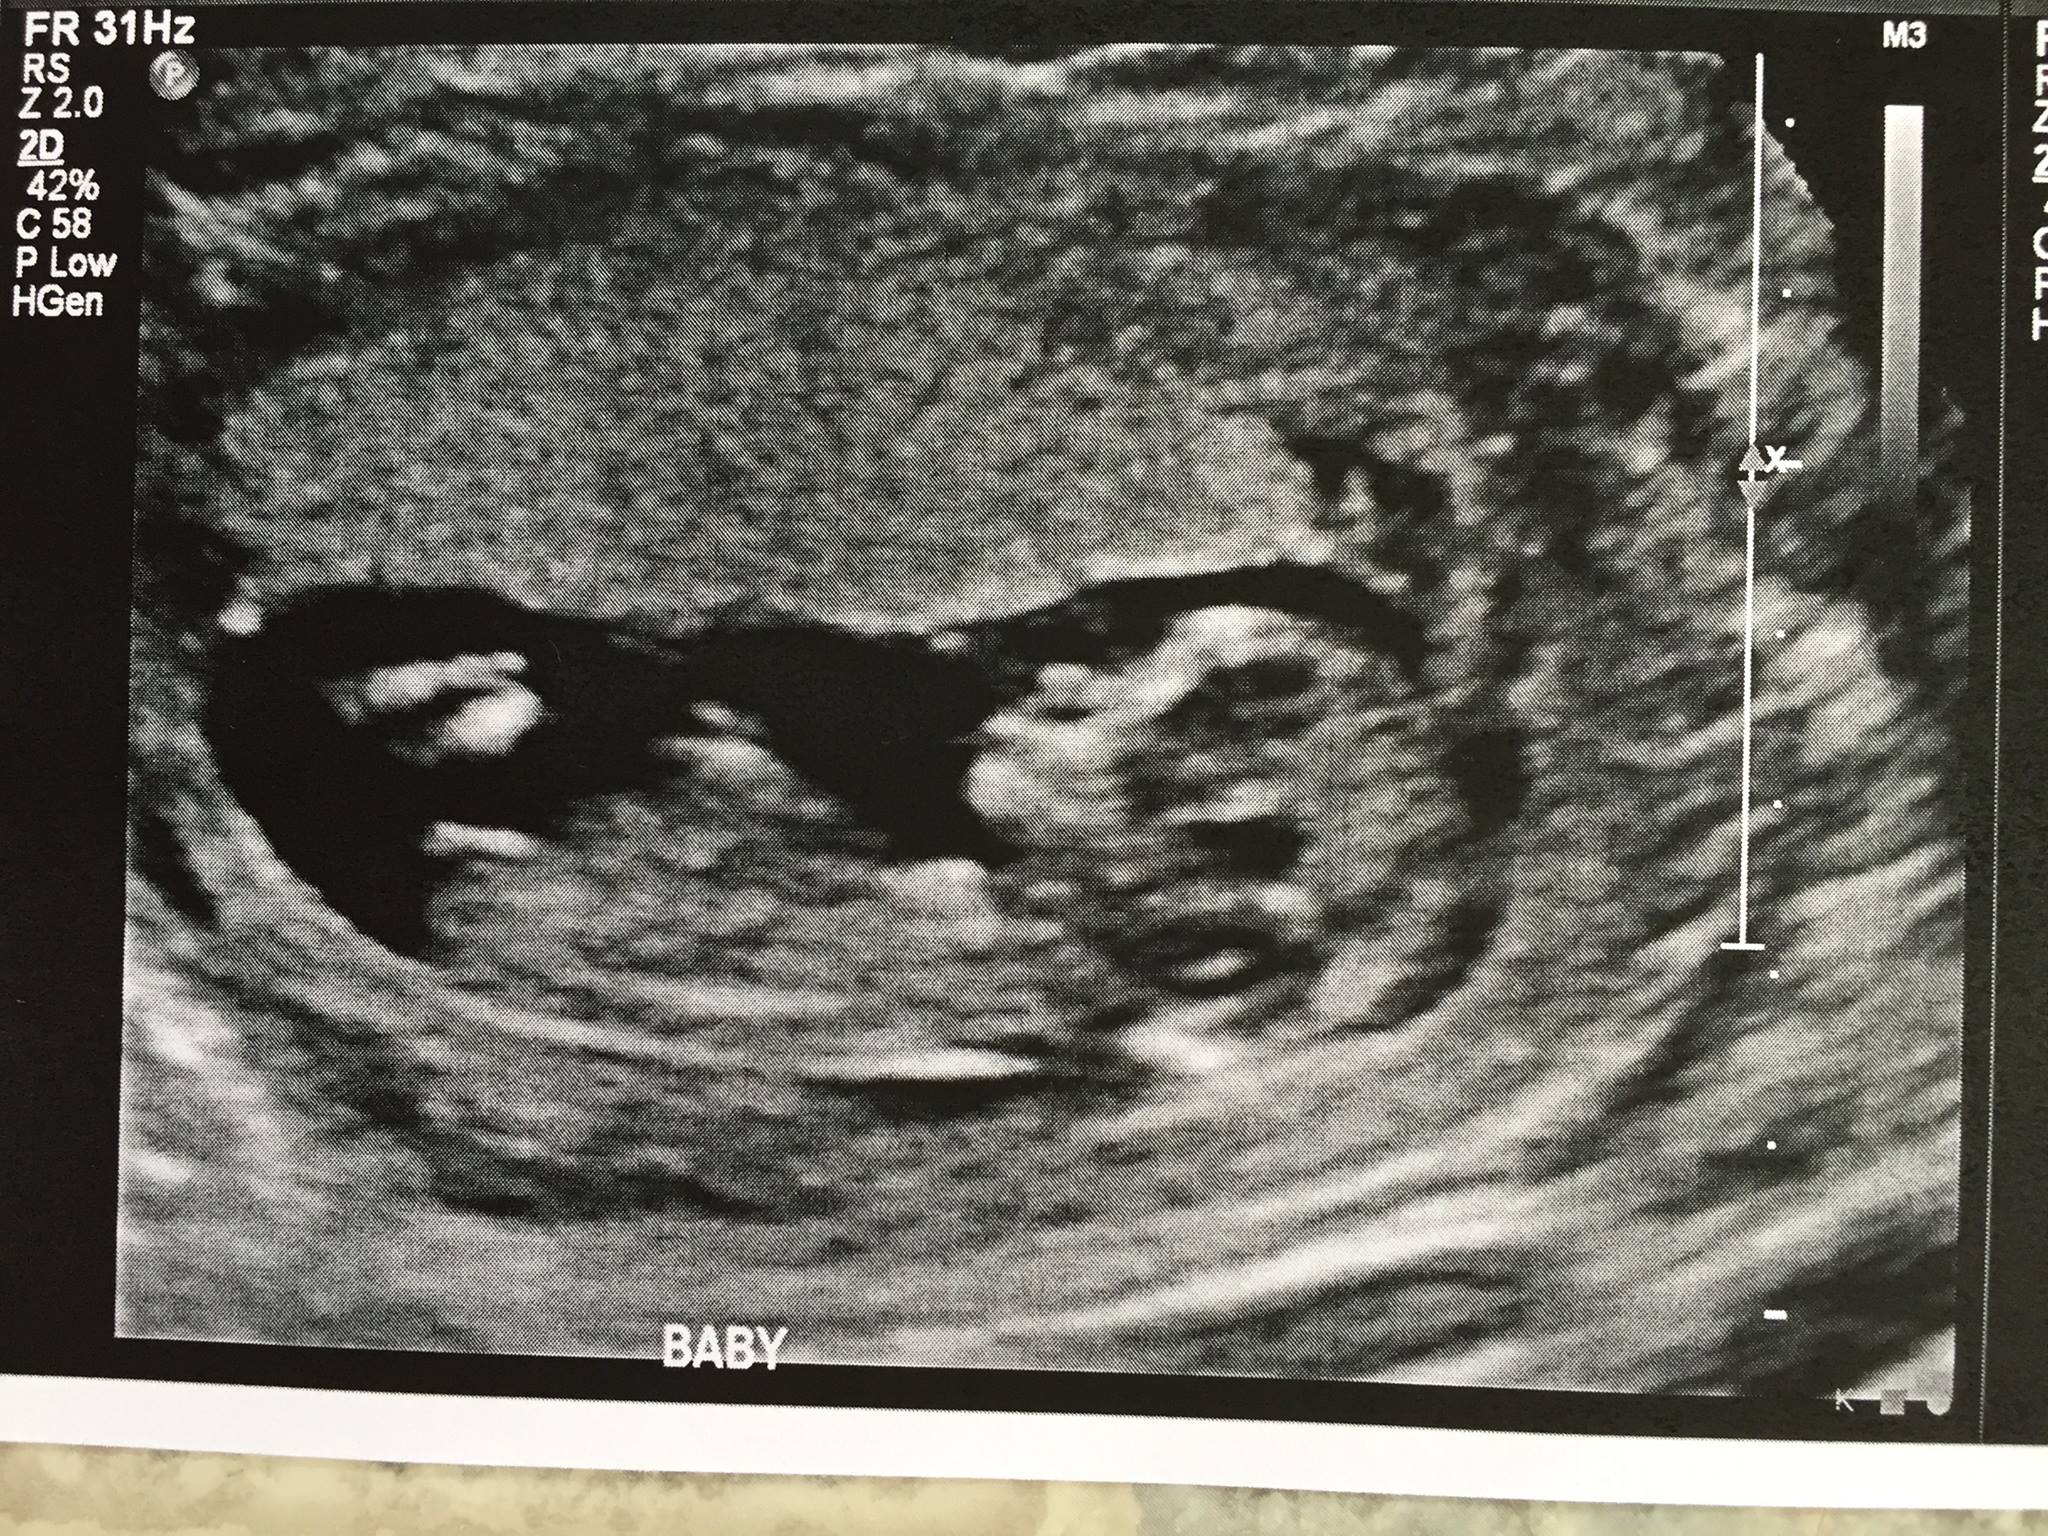

So because she's been at a fertility clinic and had some spotting, she ended up having an ultrasound at 11 weeks and 12.5 and got a nub shot at both. Super rare! And we found the difference between the nub in both images quite shocking.

This is proof that a nub shot before 12 weeks is NOT going to be a good predictor. We were pretty split on the 11 week ultrasound, but given it was pointed upward many of us were convinced boy. The theory was that once it goes up it won't go back down, and we even thought we saw testicles in one of the shots.

You can see from the 12.5 week ultrasound that this baby is ALL GIRL! So fascinating!

11 weeks nub

11 weeks - thought we could see testicles

12.5 weeks - GIRL NUB - no anatomy scan needed lol!